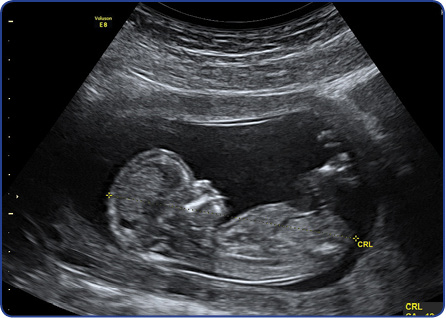

An ultrasound scan in the first half of pregnancy can count the number of babies, check where the placenta is and help to know more accurately in which month you can expect the baby to be born.